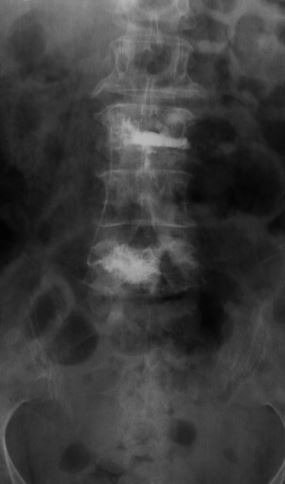

A young lady who has had previous back surgery presented to us with a new disc herniation at the same level. Her previous microdiscectomy had required an extended hospital stay because of medical complications with the patient. She had tried ample physical therapy and injections without any pain relief. She had been missing work for multiple months and was concerned she would lose her job.

She opted for the endoscopic posterolateral discectomy. Under local anesthesia [similar to dental work], the discomfort is minimized with the injected numbing medications. A small camera was placed next to the herniated disc while the patient was awake; the herniated disc was then removed. The patient felt immediate significant relief of her pain; the strength in her leg was back to normal, and she no longer felt any numbness in her legs.* She was able to go home in a few hours; about 3 months after the procedure, the patient continues to be pain free and is back to her normal activities.